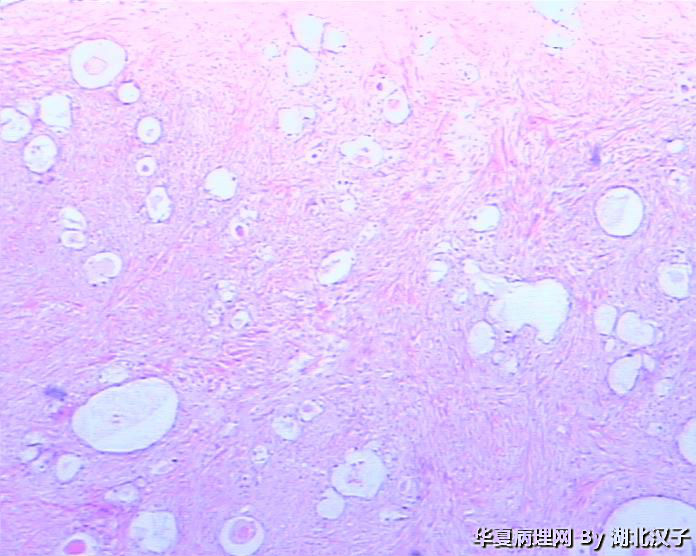

宫颈肿物,46岁,发现6月